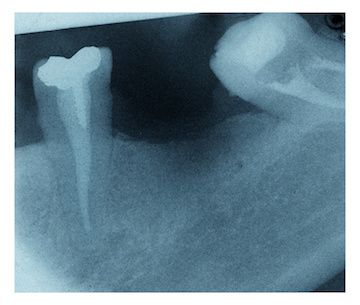

With the promising results of the initial study, the researchers next moved on to test autologous transplantation using canine stem cells. Deciduous teeth were extracted from a 30-day old dog, allowing for the generation of tooth germ from the dog’s own tooth cells. After two days of cell culture, the tooth germ was implanted back into the dog’s mandible, resulting in tooth eruption 180 days later.

Interestingly, micro-CT analysis of the new tooth showed its formation was almost identical to that of a natural tooth. Further testing revealed the structure and chemical composition matched that of natural teeth. Finally, subjecting the regenerated tooth to mechanical force resulted in a response consistent with proper physiological functioning of the periodontal ligament.